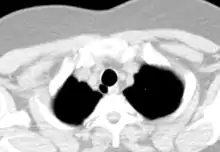

Tracheal diverticulum as seen on axial CT imaging